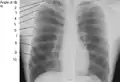

X-ray image of a human chest, with ribs labelled